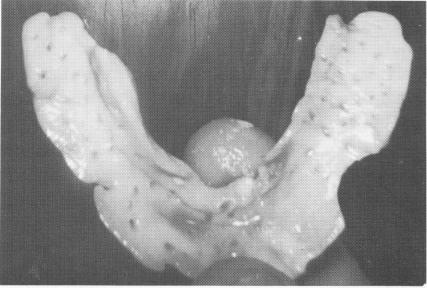

Fig. 12-8. A cold cure acrylic tray is molded directly to the exposed bone (Linkow) and removed before the heat sets in. Note the relief areas on both sides allowing for freedom of the neurovascular bundles that exit the mental foramina.

2 Cold cure acrylic tray molded directly to exposed jaw bone